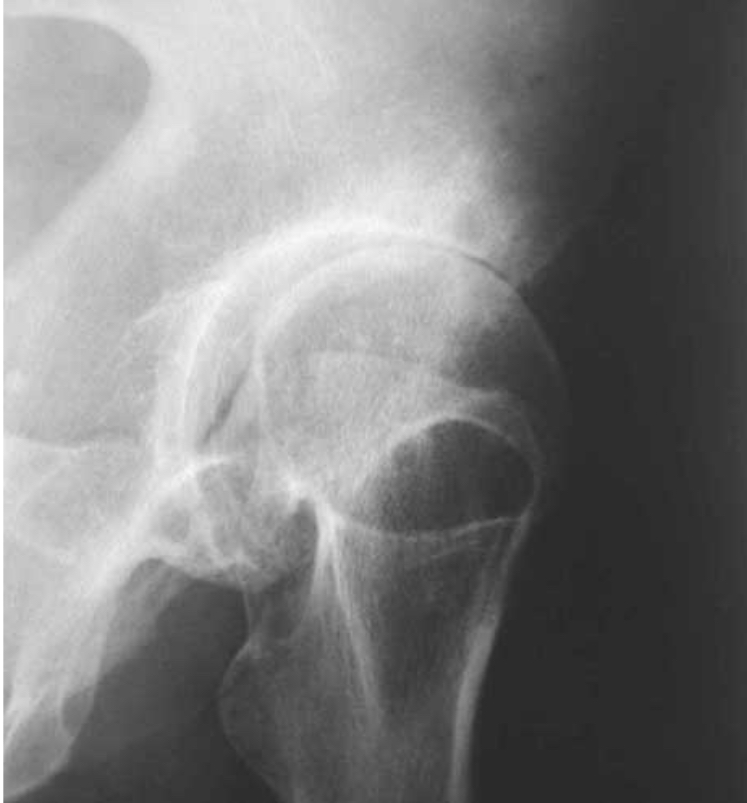

Coxarthrose bilatérale

pincement supéro-externe de l’interligne coxo-fémorale bilatérale

Coxarthrose destructrice rapide

pincement supéro-externe de l’interligne coxo-fémorale